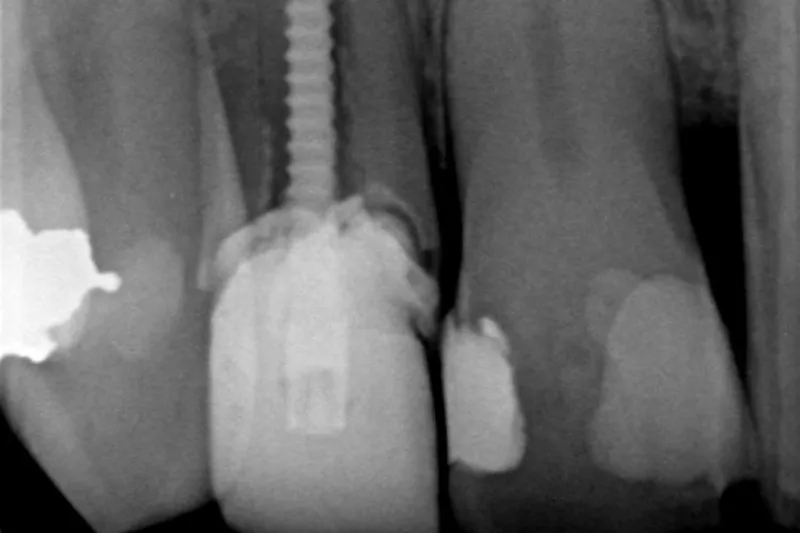

Hensigten med at foretage en rodbehandling er at bevare en naturlig tand; men i nogle tilfælde ender det alligevel med, at den rodfyldte tand må ekstraheres.

Ved logistisk regressionsanalyse fandt man, at en række faktorer havde signifikant sammenhæng med tandtabet. Fx patientens alder (OR for patient > 75 år var 2,2; P < 0,001), og tandtypen (OR for underkæbemolar var 2,0; P < 0,001. For overkæbemolar var OR 1,9; P < 0,001). Mest åbenlys var dog sammenhængen med den restaurative behandling, tænderne havde fået efter rodbehandlingen.

Sammenlignet med en indirekte koronal restaurering og støbt stiftopbygning var risikoen for tandtab lidt mere end tre gange højere både ved tænder uden restaurering (OR = 3,2; P < 0,001) og ved tænder med plastfyldning og direkte stiftopbygning (OR = 3,2; P < 0,001). For tænder med plastkrone uden opbygning var OR 2,2 (P < 0,001).

Forfatterne anbefaler, at man er opmærksom på valget af restaurering, især efter rodbehandling af molarer på ældre personer.